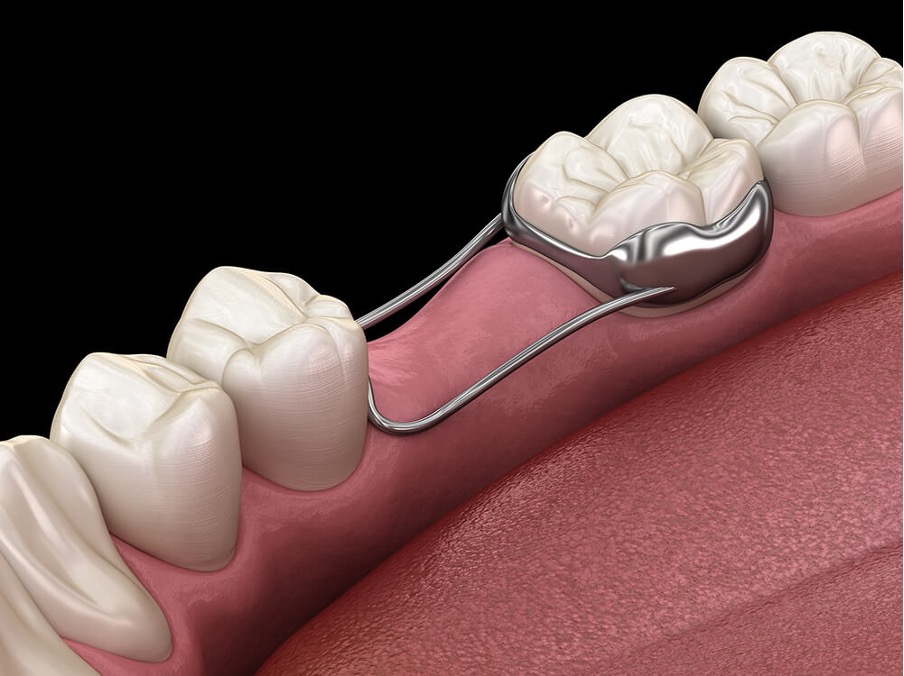

乳歯にはあとから生えてくる永久歯を正しい位置に導くガイドの役割があります。そのため、虫歯やケガによって早期に乳歯を失ったときに使うのが保隙装置です。永久歯の生えるスペースを確保して、永久歯がまっすぐ生えるように導き、歯並びが乱れるのを防ぎます。

歯を舌側から固定する装置です。あとから生えてくる永久歯が正しい位置に並ぶように顎のスペースを確保するために装着します。

失った乳歯の空間を保つために歯にバンドを蒔いてループをつけるのが「バンドループ」で被せ物にループをつけるのが「クラウンループ」です。